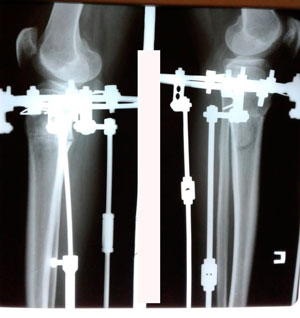

рентген в 60 дней.

Вложения

image-28-05-20-02-47-1.jpg

image-28-05-20-02-47.jpg